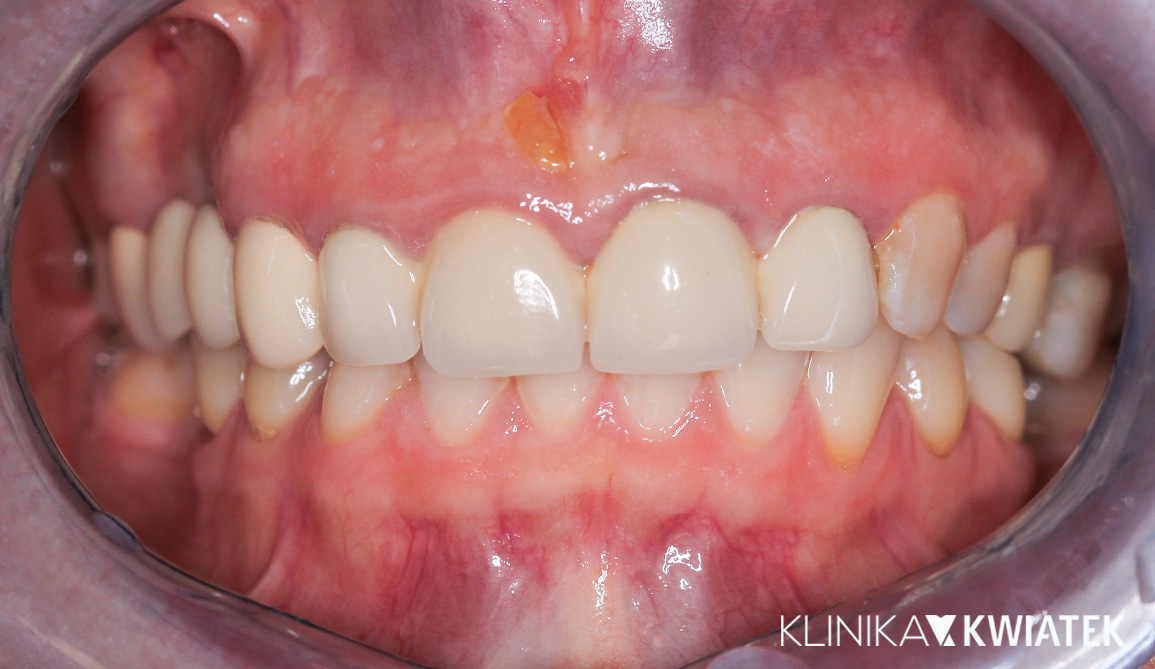

PO

Pan Jakub zgłosił się do kliniki z wadą zgryzu oraz licznymi problemami wynikającymi z nieprawidłowego ustawienia zębów. Leczenie wymagało współpracy specjalistów z kilku dziedzin stomatologii, precyzyjnego planowania oraz konsekwentnej realizacji kolejnych etapów terapii.

Dzięki ogromnej determinacji Pacjenta, który pomimo dużej odległości regularnie przyjeżdżał na zaplanowane wizyty, możliwe było przeprowadzenie kompleksowego leczenia, którego efektem jest doskonale zbalansowany zgryz oraz spektakularna i w pełni naturalna metamorfoza uśmiechu.